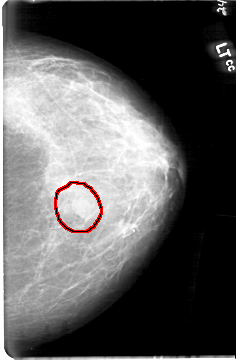

D_4092_1.LEFT_MLO

LEFT_MLO LINES 5386 PIXELS_PER_LINE 3721 BITS_PER_PIXEL 12 RESOLUTION 43.5 OVERLAY

FILE: D_4092_1.LEFT_MLO.OVERLAY

TOTAL_ABNORMALITIES 1

ABNORMALITY 1

LESION_TYPE MASS SHAPE OVAL MARGINS OBSCURED

ASSESSMENT 0

SUBTLETY 4

PATHOLOGY BENIGN

TOTAL_OUTLINES 1

BOUNDARY